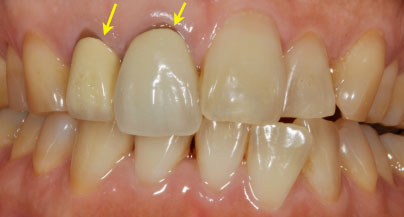

画像の患者様は歯の色と矢印で示された差し歯の色と適合の改善を希望されていました。

最初に約10日間のホワイトニングをして歯の色を改善しました。

次に差し歯の交換を変化した綺麗な歯の色に合わせて交換しました。

全体として約3週間くらいで治療が完了致しました。

とても自然な仕上がりになりました。

定期的にチェックと歯面の清掃を細かく行う事によってホワイトニングの持続力が長続きいたします。